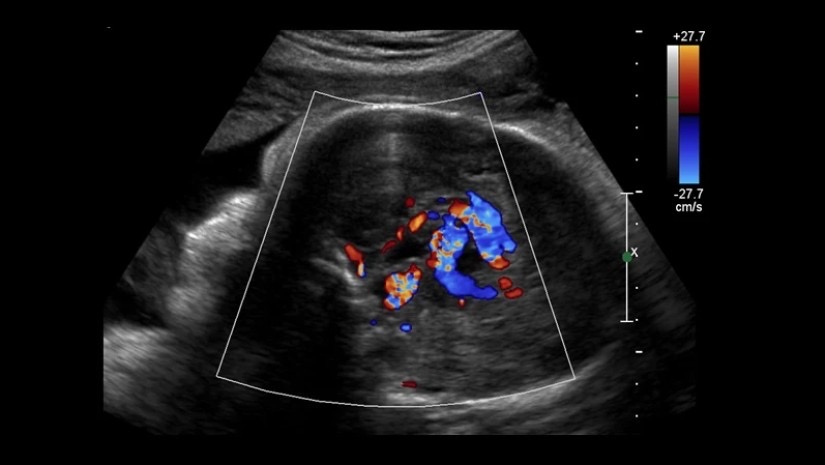

იშვიათი პრენატალური (დაბადებამდელი) მდგომარეობის სამკურნალოდ, ბოსტონის ბავშვთა ჰოსპიტლისა და Brigham and Women’s ჰოსპიტლის ქირურგებმა მეთოდი, სახელად ემბოლიზაცია გამოიყენეს. დაავადებას გალენის ვენის მალფორმაციას (VOGM) უწოდებენ და წარმოადგენს სისხლძარღვთა ანომალიას, რომლის გამოც, ბავშვის დაბადების შემდეგ, მისი თავის ტვინის გარკვეულ ნაწილში სისხლი სახიფათოდ ჩქარა მოძრაობს. პროცედურის წარმატება აჩენს იმედს, რომ ამ დაავადების მკურნალობა იქამდე იქნება შესაძლებელი, ვიდრე გართულებათა რისკი გაიზრდება.

„მიმდინარე ცდაში, გალენის ვენის მალფორმაციის დაბადებამდევე სამკურნალოდ ვიყენებთ ულტრაბგერით მართვად საშვილოსნოსშიდა ემბოლიზაციას. მკურნალობის პირველ შემთხვევაში, აღფრთოვანებული დავრჩით პათოლოგიის აგრესიული შემცირებით“, – ამბობს ბოსტონის ბავშვთა ჰოსპიტლისა და ჰარვარდის სამედიცინო სკოლის ნეიროინტერვენციული რადიოლოგი დარენ ორბახი.